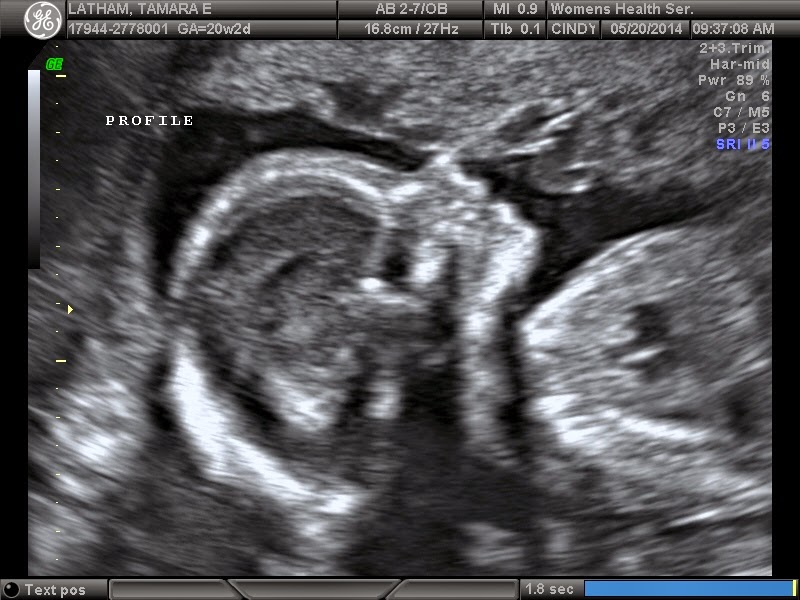

| [Lois @ 20 weeks] |

We named her at our ultrasound when we found out she was a girl, and have been giddy with excitement about our little Lois ever since!

Isn't she stunning??